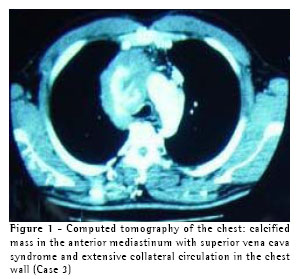

A 35-year-old previously healthy male presented with headache accompanied by cervical and facial edema for seven years, the symptoms having been incapacitating for the last two years. The working diagnosis was superior vena cava syndrome, and the patient was submitted to computed tomography of the chest, which revealed a mass in the anterior mediastinum, with a calcified center, invading the superior vena cava (Figure 1). In December of 2001, the patient was submitted to video-assisted thoracoscopy and a biopsy of the mass was carried out. The results of the frozen biopsy examination were inconclusive. A definitive, reviewed anatomopathological examination revealed dense adipose connective tissue infiltrated by atypical cells. Based on the immunohistochemical test results, the differential diagnosis between infiltrative neoplasia and entrapped reactive mesothelium was inconclusive. One year later, radiotherapy was unsuccessful, and there was an enlargement of the lesion as well as formation of significant collateral circulation revealed by a computed tomography scan of the chest. The patient was subsequently submitted to median sternotomy, during which significant sclerosis and fibrosis of the mediastinum were found. Subsequently, the left brachiocephalic vein was grafted to the right atrium using an 8-mm PTFE stent (Figure 2). In the postoperative period, the patient presented signs and symptoms of congestive heart failure, which were controlled using classic measures. The patient was discharged while still being treated with warfarin and has been in outpatient follow-up treatment for two months, his symptoms being well compensated. Anatomopathological examination revealed sclerosing mediastinitis. (Figure 3)